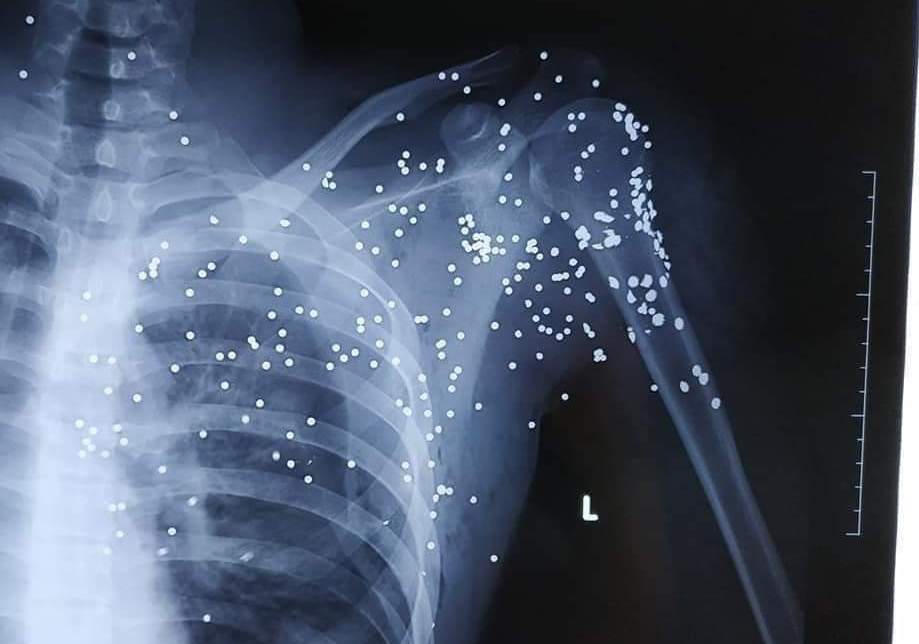

Anh Hoàng được người dân hô hoán báo gia đình đưa đi cấp cứu tại Bệnh viện Đa khoa tỉnh Thái Bình trong tình trạng đa chấn thương, tập trung ở vùng cổ, vai trái và phía trên ngực trái, mất nhiều máu. Sau khi tiến hành sơ cứu và chụp, chiếu, nhận thấy các vết đạn xuất hiện dày đặc nơi vùng phổi của nạn nhân, các bác sỹ đã nhanh chóng phối hợp cùng gia đình chuyển nam thanh niên bị nạn lên cấp cứu tại Bệnh viện Hữu nghị Việt Đức.